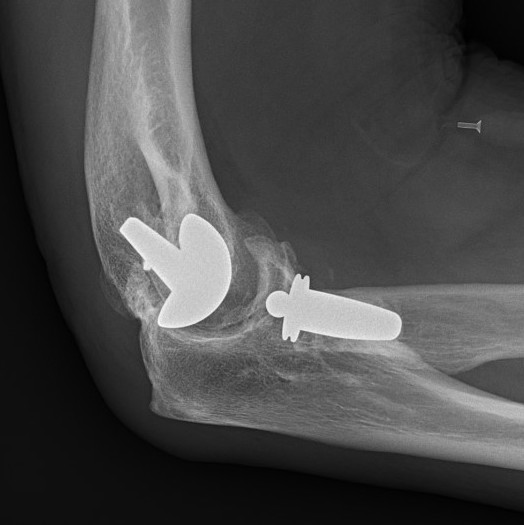

Coonrad-Morrey Discovery Elbow Latitude

Arthroplasty

4. Trial reduction

5. Insert cement restrictors / implant ulna and humeral prosthesis

6. Insert bone graft under anterior flange

7. Link components

8. Repair collaterals if needed